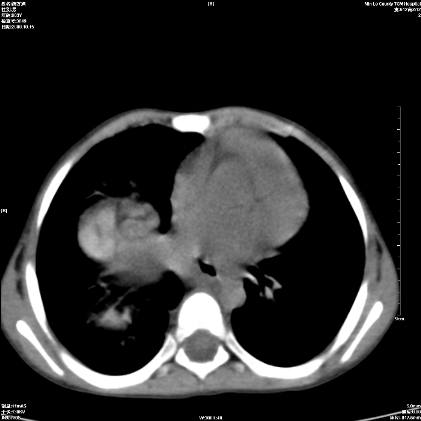

标题: PED1609:男性,3岁。彩超示肝Ca. [打印本页]

标题: PED1609:男性,3岁。彩超示肝Ca.

考虑后纵隔恶性畸胎瘤伴肝内多发转移可能性大,右侧肾上腺转移不除外.

3岁;肝低密度灶;有钙化;有转移灶;考虑肝母细胞瘤;查afp

考虑神经母细胞瘤并肝转移

考虑:1、右侧后下纵隔畸胎瘤。

2、肝脏多发血管内皮细胞瘤。

建议:增强确诊。